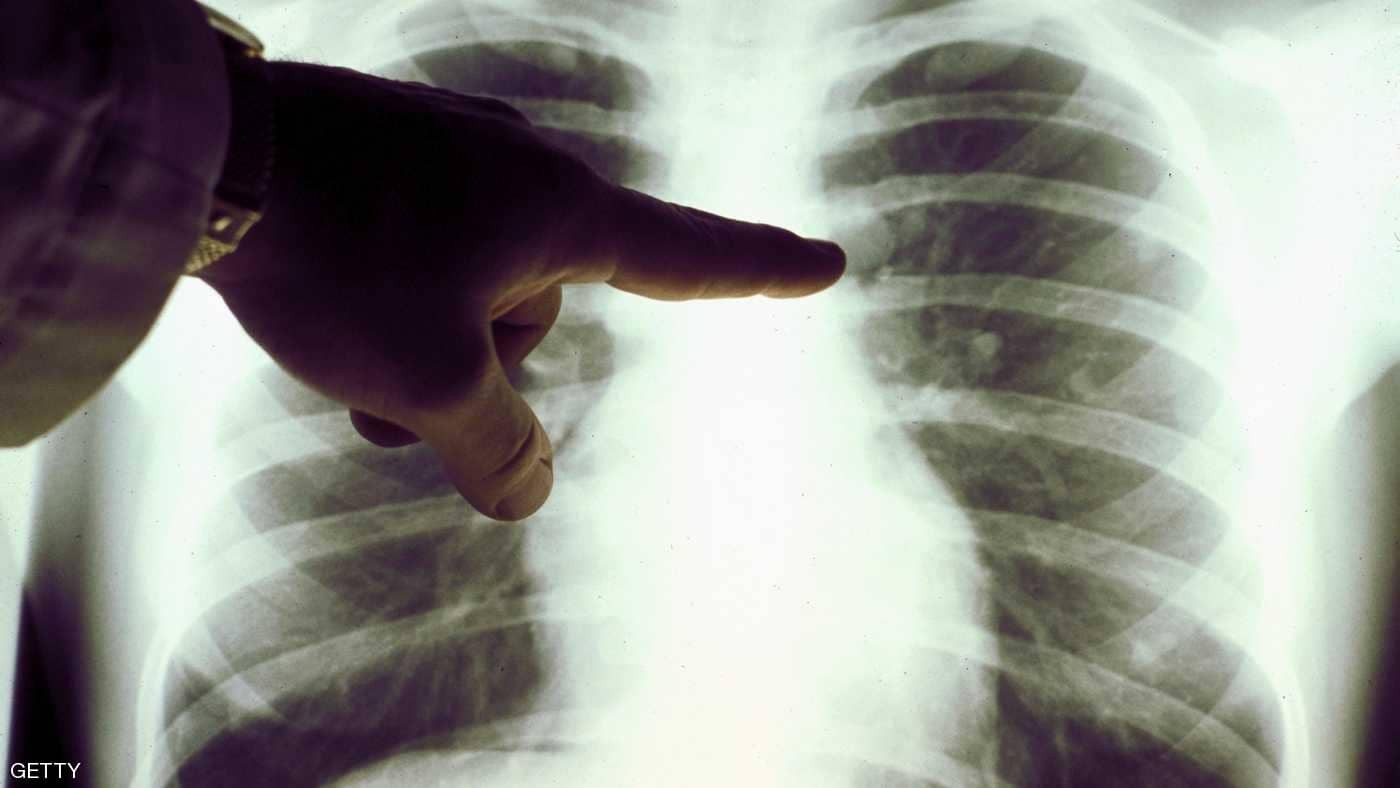

عندما نسمع عن سرطان الرئة، يتبادر إلى الذهن سريعا تدخين السجائر كمسبب رئيسي، لكن العلماء وجدوا أيضا أن بعض الأغذية يمكن أن تؤدي إلى هذا المرض الخطير.

وأظهرت دراسات علمية صدرت حديثا، أن العادات الغذائية للفرد قد تسهم كذلك في فرص إصابته بسرطان الرئة.